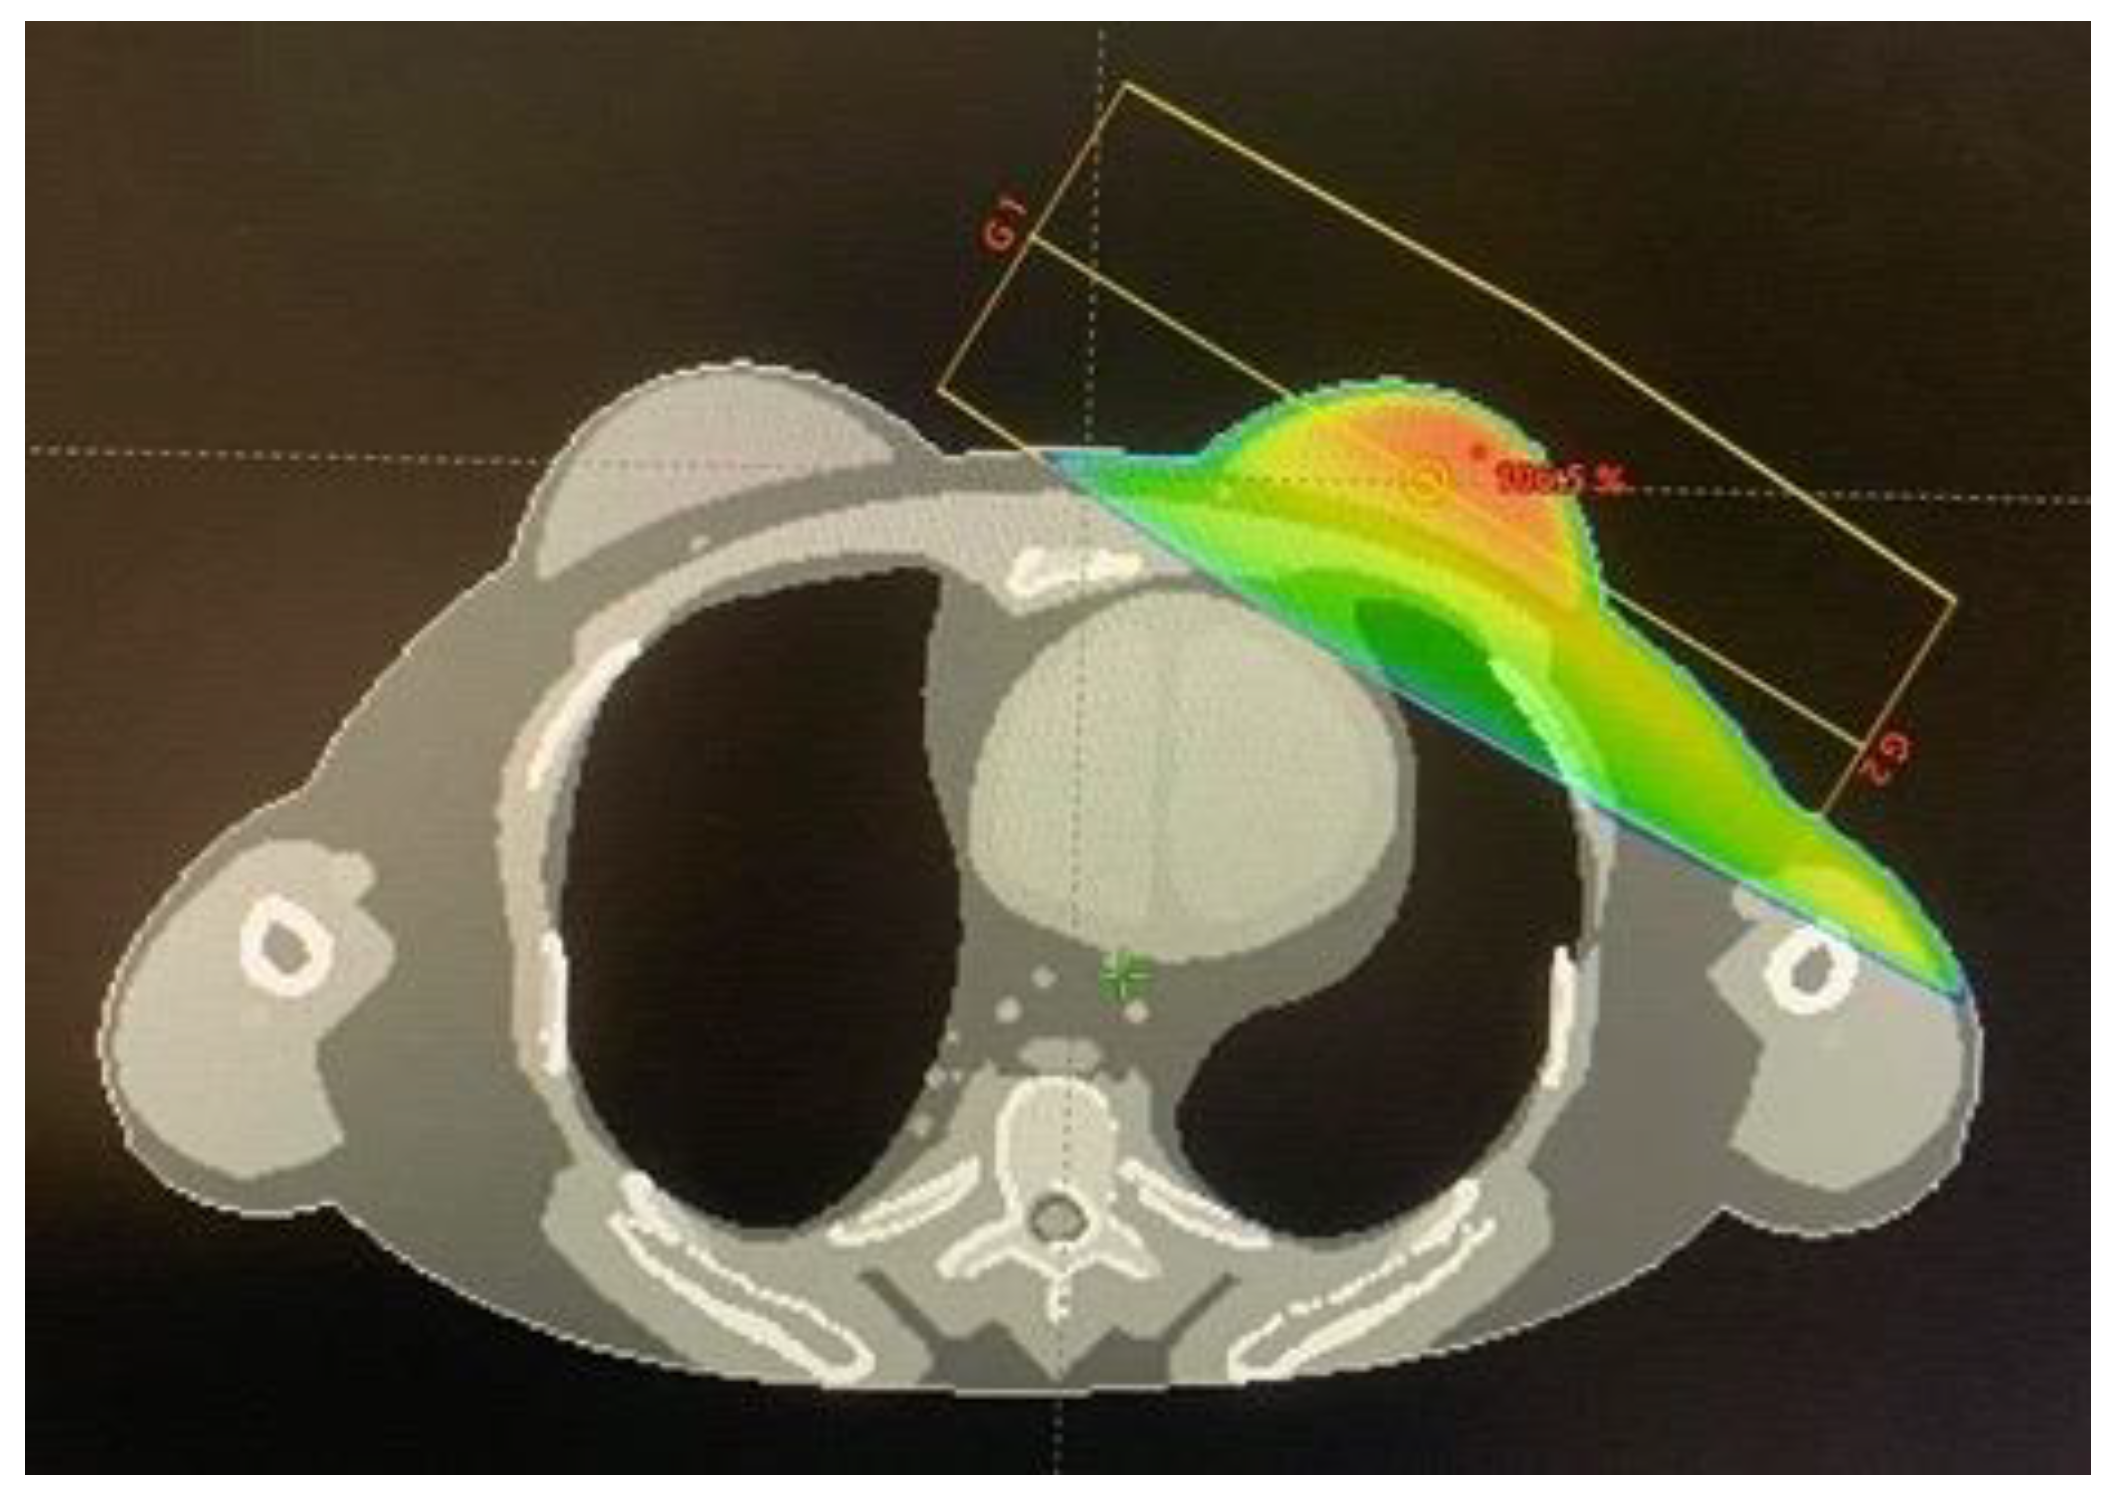

2.1. Treatment Planning